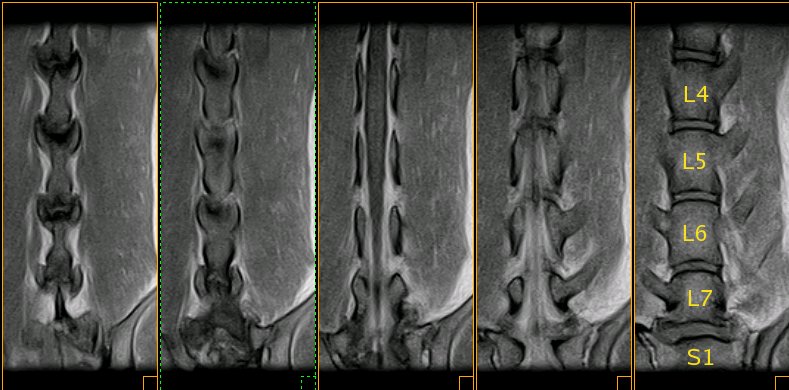

Resonancia magnética (SE T1 sagital) de la columna lumbar |

Resonancia magnética lumbo-sacra de pastor alemán |